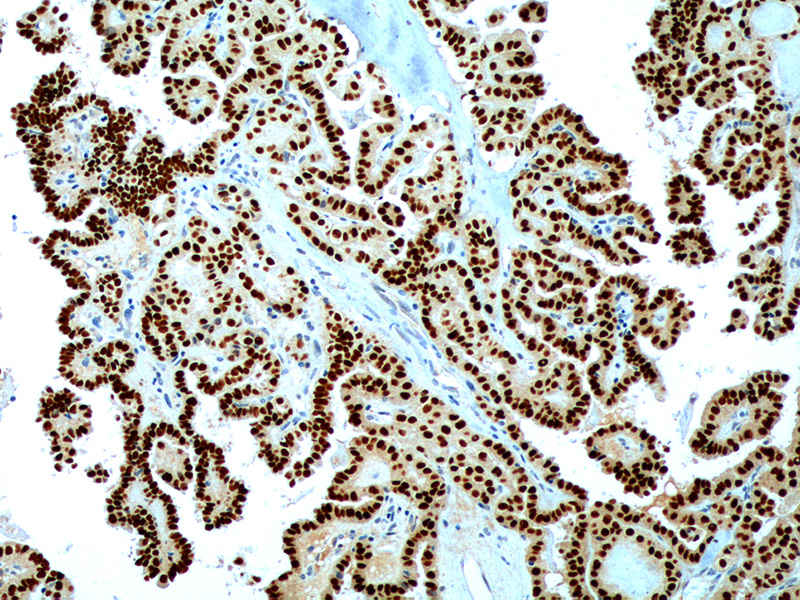

图片:

PAX-8 Antibody (P1004) on Ovary Tumor